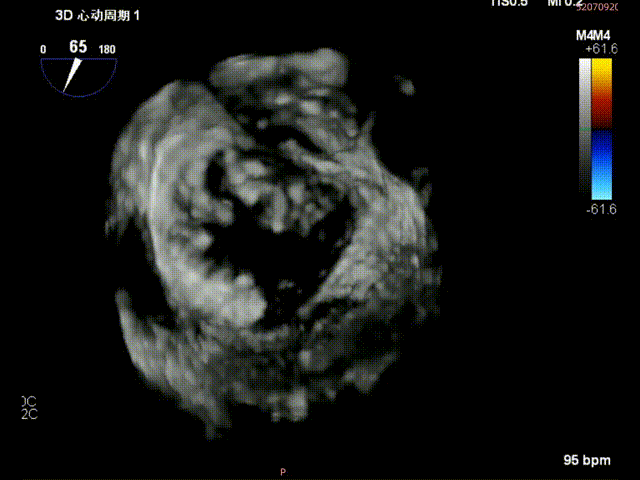

调整第二枚NeoNova ® C6夹合器orientation,将其送至1区内侧残余脱垂处,定位后 Clasp 捕获瓣叶,注意瓣叶张力,缓慢收紧 Paddle ,食道超声3D界面评估组织桥稳定,可见脱垂基本消失,未见明显反流来源。

第二枚夹合器夹合后3D血流

撤出系统后复查食道超声示: 瓣叶钳夹稳定度良好,脱垂消失,未见明显反流,测量平均压差1mmHg,肺静脉逆流消失。达到预期介入效果,手术成功。